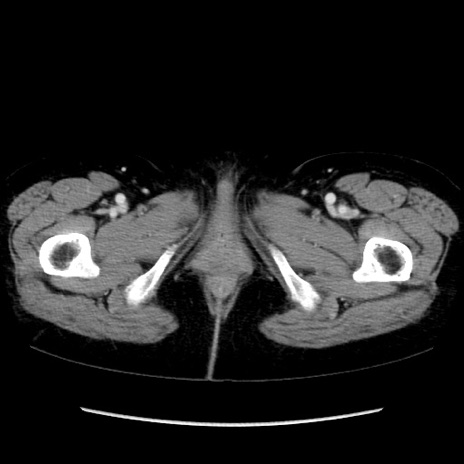

症例32(横断像)

【症例】40歳代 女性

【主訴】上腹部痛、嘔気・嘔吐

【現病歴】約9時間前頃から急に上腹部痛、嘔気、嘔吐が出現。改善しないため救急要請。

【既往歴】子宮頚癌(広汎子宮全摘術、放射線療法)、腸閉塞

【身体所見】腹部:平坦、軟、腸雑音亢進、上腹部を中心に腹部全体に圧痛あり。

【データ】WBC 8400、CRP 0.03